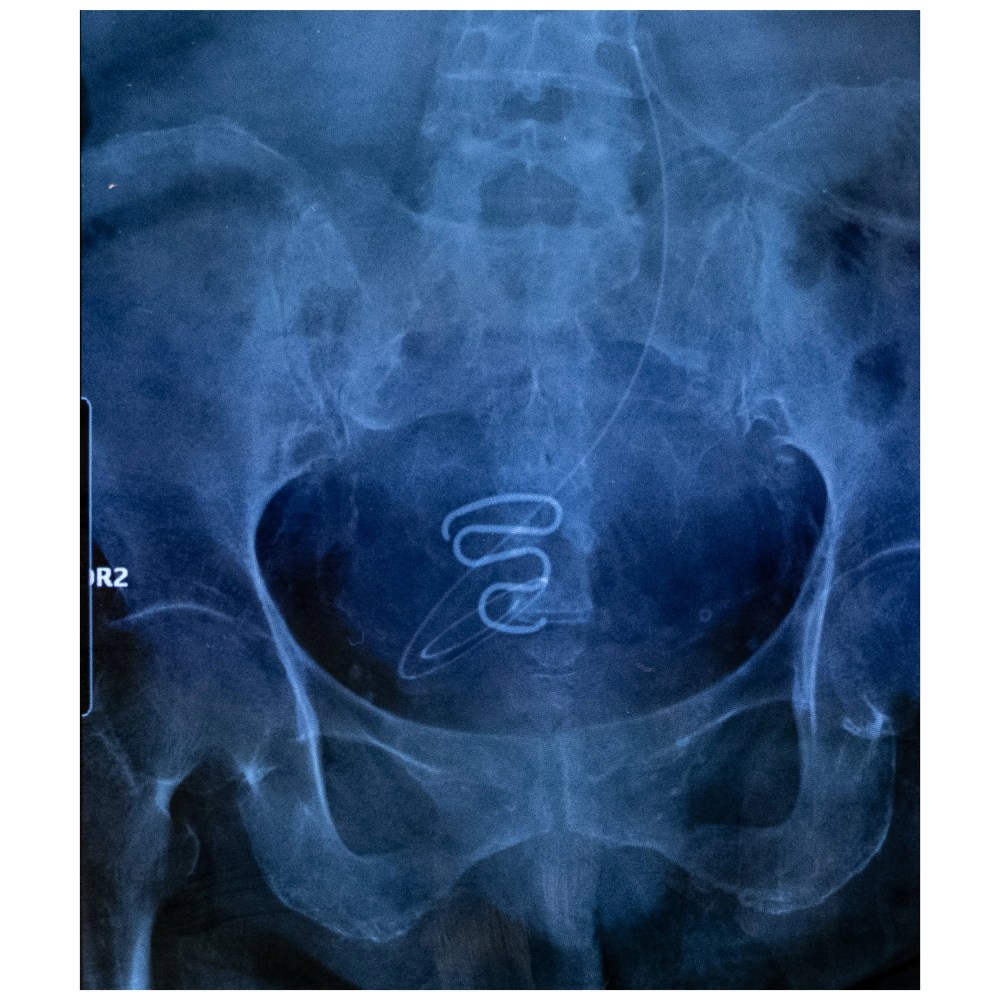

« Dans ce livre, explique en préface la journaliste Anne-Françoise Hivert, Juliette Pavy rassemble les photos tirées de ses reportages sur la stérilisation forcée, plusieurs fois primés. Elle y fait le portrait de la psychologue Naja Lyberth et de ses sœurs d’infortune. Elle traque les stérilets oubliés dans le corps des femmes, révélés à la radiographie – longs fils en serpentin, incrustés dans leur utérus. Elle retrouve de vieux instantanés rappelant que les jeunes filles avaient à peine atteint l’âge de l’adolescence. »

Des stérilets ont été posés de force sur des adolescentes encore vierges, les femmes ont tu pendant longtemps ce traumatisme, dont la société danoise prend aujourd’hui conscience.

Des langes, des bébés, et la spirale d’un stérilet leur interdisant d’être enceinte – reproduit de façon stylisée sur le dos de la couverture, c’est un serpent de cuivre.